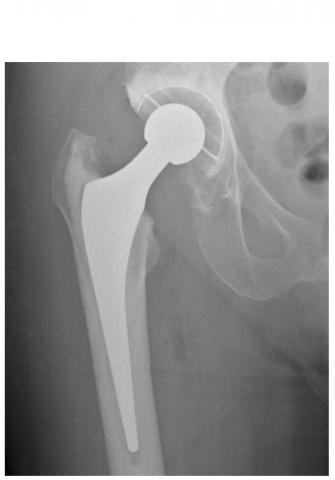

Des variations considérables en fonction des types d’arthroplasties : un remplacement de la hanche comprend principalement 2 composants (col, cavité) mais reste variable dans la manière dont ces pièces sont fixées à l'os, ainsi que dans les matériaux utilisés pour consolider la surface d'appui. Idem pour l’arthroplastie du genou, l’arthroplastie totale va remplacer toute la surface articulaire du patient, tandis qu'une prothèse de genou unicondylienne ne remplace que la partie endommagée du genou. Bref, les variations sont considérables en matière d’arthroplasties de la hanche et du genou, cependant ces facteurs ont bien été pris en compte dans l’analyse.

Arthoplasties de la hanche : L’analyse a porté au total sur les données de 215.676 patients, suivis pendant au moins 15 ans, 74.052 patients suivis pendant au moins 20 ans et 51.359 suivis pendant au moins 25 ans.

- 89% des arthroplasties de la hanche ont « duré » 15 ans, 70% ont duré 20 ans et 58% ont duré 25 ans.